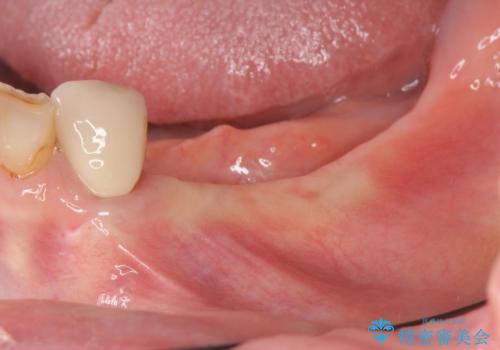

- 歯を虫歯により失い、「とりあえず入れ歯を入れたが,とにかく噛めず食事が全く楽しくない」またしっかりと噛みたいと希望され来院されました。

入れ歯を外し、またしっかりと噛んで食事を楽しめるようになるためにインプラントによる治療を計画します。

インプラントを埋入することで入れ歯のように取り外しをする必要がなくしっかりと噛めるような状態になり、大変治療結果に満足していただくことができました。